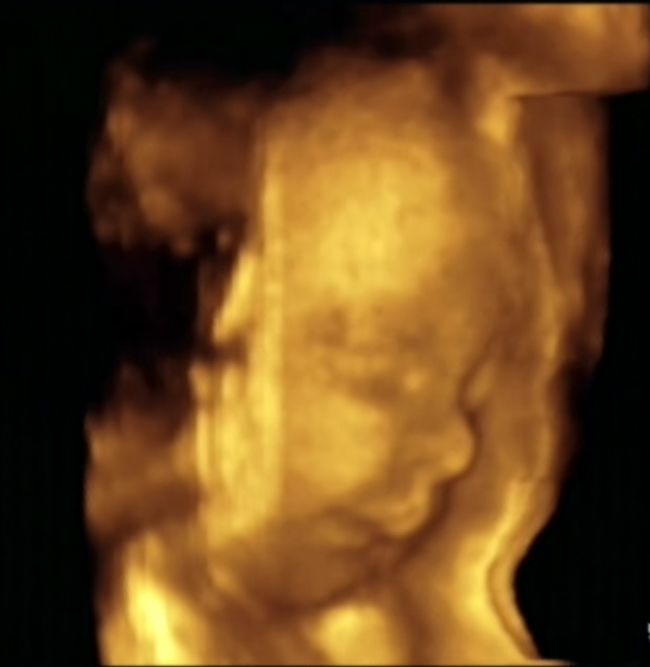

Drinken: